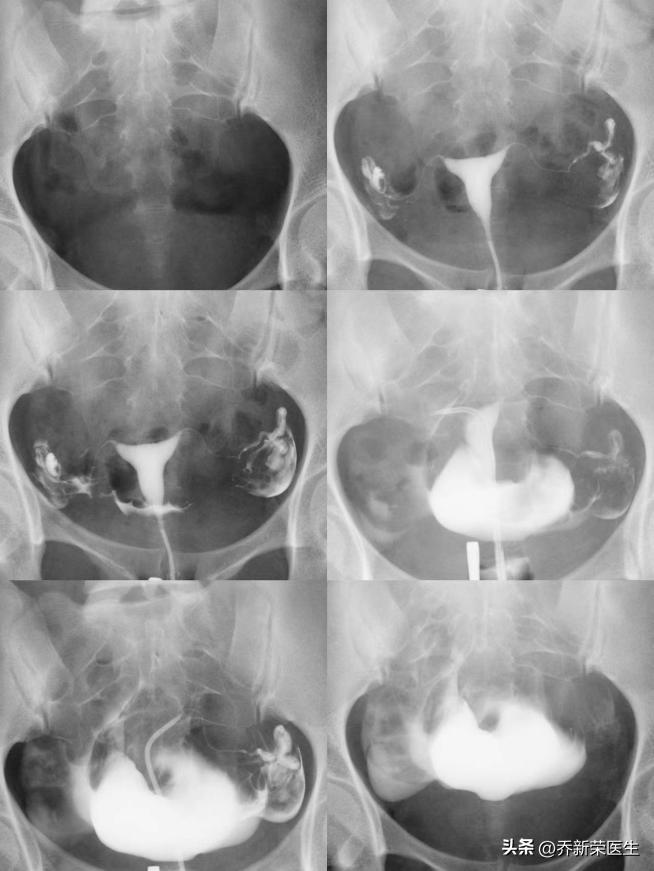

我听完后紧紧地跟上了她的话,殊不知输卵管堵塞的原因主要是由于妇科炎症感染所引起的,最常见的是反复发生的霉菌性阴道炎、滴虫性阴道炎、细菌性阴道炎、宫颈炎等,这些炎症感染由于女性盆腔的特殊位置会上行感染,继而引起子宫输卵管的炎症,从而造成管腔或者输卵管周围发生粘连,炎性分泌物增加迁延不愈,长期存在反复刺激形成慢性的炎症,从而导致输卵管的堵塞。我随即给的建议做个X线下不插管子宫输卵管造影检查进一步明确输卵管病通畅情况和初步评估输卵管病因,如果输卵管存在堵塞建议行输卵管介入治疗,一次性解决输卵管问题。

患者听从了我的建议,当日X线下不插管子宫输卵管造影检查显示宫腔正常,双侧输卵管通而极不畅,随即行无创输卵管介入治疗,结果双侧输卵管通畅,病因考虑非特异性炎症,双侧输卵管蠕动拾卵功能稍差,术后建议加强营养,补充蛋白质,增强免疫力;中医中药理疗,必要时根据情况两个月后试孕。